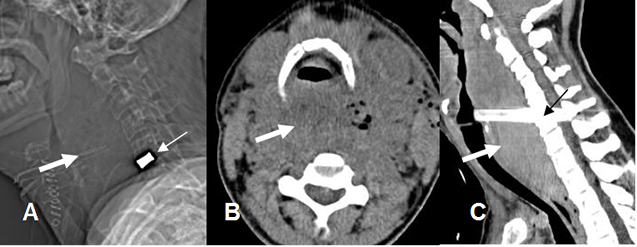

Ocurren en el PostQx inmediato y su drenaje es una urgencia, porque puede causar déficit neurológico. (30). (Fig 129A, 129B y 129C).

Fig 129A. Hematoma postquirúrgico.

A: Rx lateral, B: TAC axial y C: TAC reconstrucción sagital. PostQx de prótesis de disco, en el espacio C5-C6. (Flecha delgada). Formación de colección prevertebral, que desplaza y comprime la vía aérea. (Flecha gruesa).